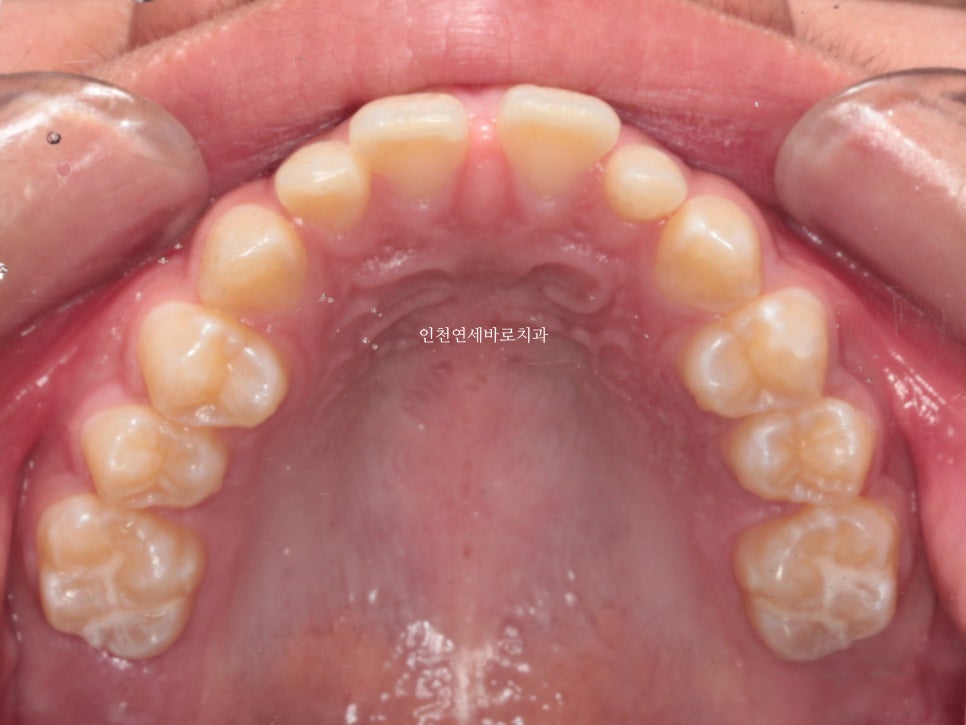

추가적인 #악궁확장장치 등은 사용하지 않았습니다.

#클린체크 라고 하는 인비절라인 전용 디지털 치료계획 프로그램상에서 치료계획을 수립한 결과 추가적인 악궁확장장치는 필요없었습니다.

한번의 재제작을 했던 환자분입니다.

재제작 소요기간 한달을 포함해서 환자분이 병원에 오고 딱 1년만에 치료가 마무리 되었습니다.

문제가 되었던 오른쪽 어금니 교합도 좋게 마무리 하였습니다.

악궁확장장치는 사용하지 않았습니다.